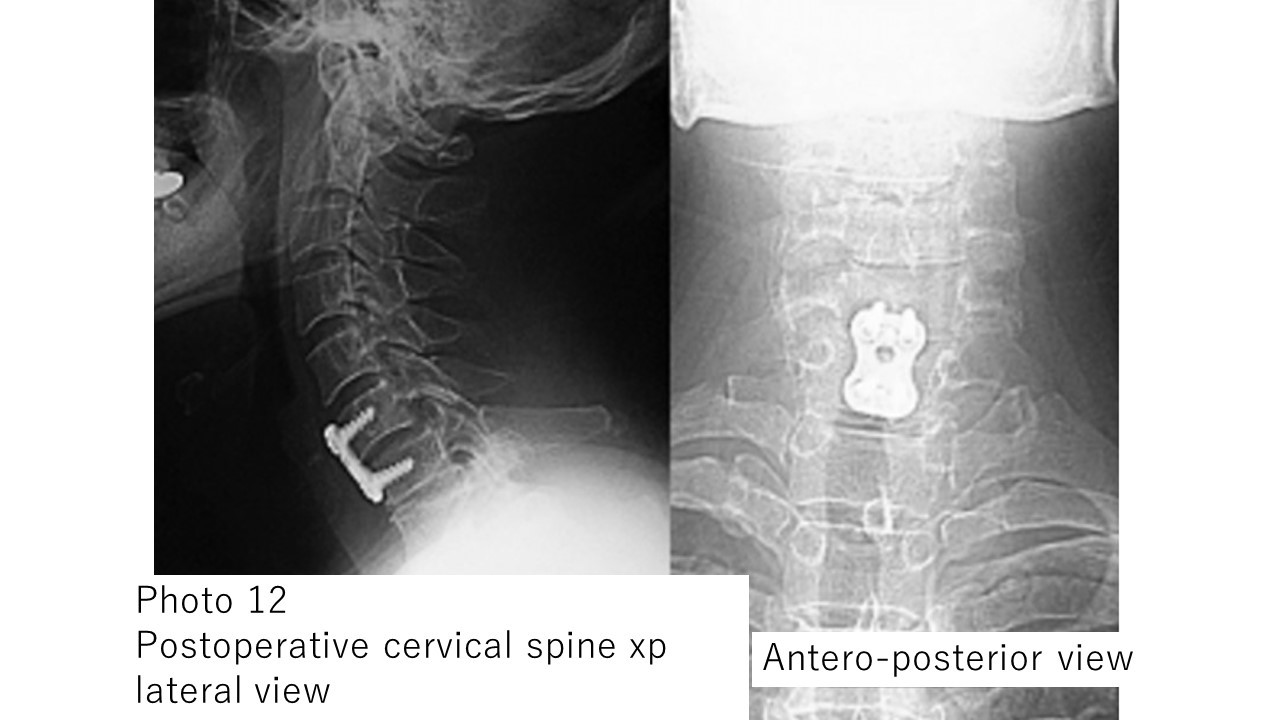

Photo 12: Plain X-ray image of the cervical spine after surgery for the patient in Photo 11

。